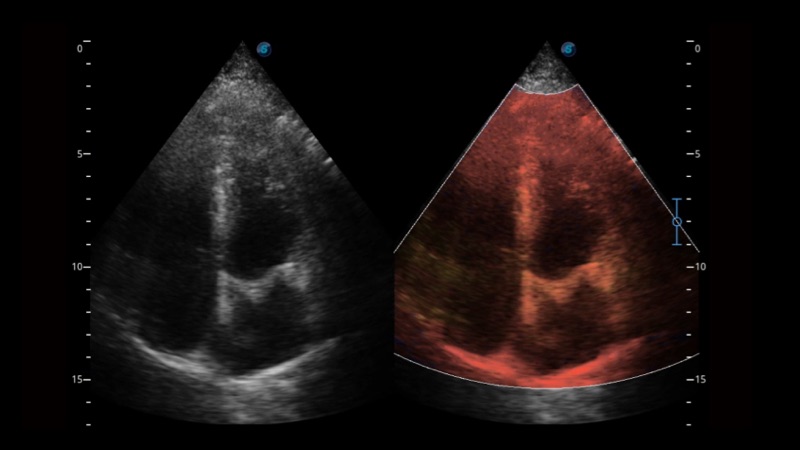

开立医疗通过不断的技术创新,为大众的生命健康提供持续关爱。P12 Plus采用全新一代超声成像平台,新平台旨在将真实还原组织解剖结构作为首要目标。平台采用全新集成化硬件模块,搭载新一代芯片,系统性能得到大幅提升,为您的诊断提供了丰富的临床信息。优异的图像表现,丰富的探头配置,全面的应用功能,为您日常诊断提供了可靠的助手。

凭借开立医疗先进的成像技术和优异的探头技术提供的清晰的图像表现,您可以更自信地做出临床决策。